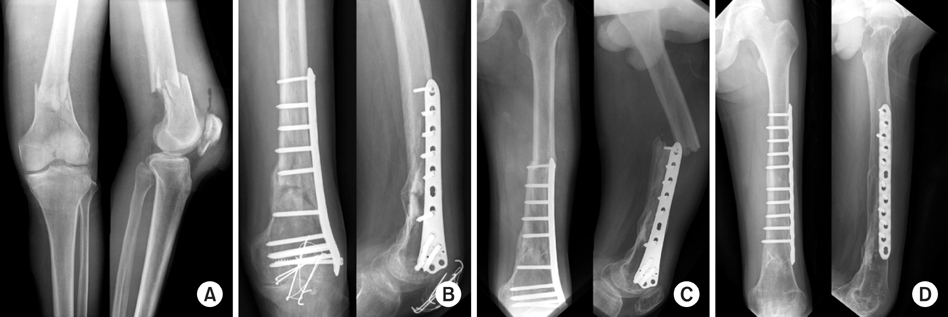

Summary of patient demographics, injury and fracture types, and outcomes

The clinical outcomes of the Schatzker and Lambert assessment